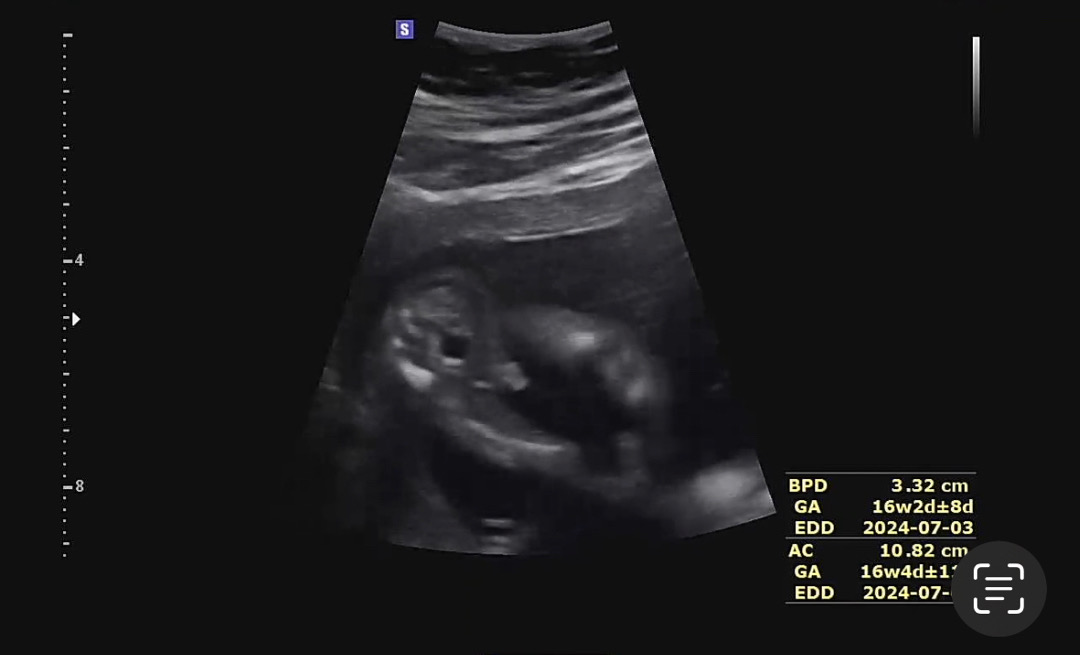

왕고chu 확정 받고 왔어요

오늘 기다리던 16주 검진인데 초음파 기기 배에 대자마자 똭! ㅋㅋ 너무 존재감이 커서 한참 웃었네요 ㅎㅎ 이제 옷 살때 남자아이 옷으로 준비하면 되겠어요!!